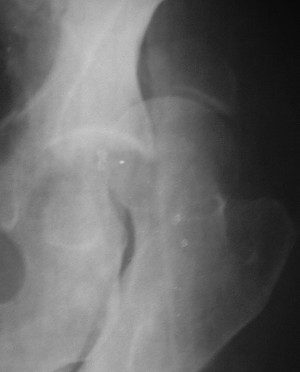

Привет! Вот недавно прооперировали похожий на ваш случай - впадина + шейка (правда у нас впадина поперечный+задний край). После травмы прошло 4 недели. мужчине 46 лет. С такой комбинацией все показания к первичному протезированию. Морально и технически мы к этому уже созрели.Но больной не собрал денег на протез. Выполнили остеосинтез впадины и шейки, прекрасно понимая, что головка вскоре рассосется, мы хотя бы надемся что к этому времени таз срастется, как говорится создали все условия для дальнейшего протезирования (может, и протез в последующем подешевле будет, в смысле, без укрепляющего кольца?). Привет Рункову!

Отправитель: Рунков 27 Сентябрь 2005, 09:57

Привет Алекей! Сделано неплохо, поздравляю, хотя второй винтик можно было бы и подлиннее в шейку загнать! Пара вопроов: доступ такой же? головка была свободной или висела на капсуле?

Отправитель: Алексей Смирнов 27 Сентябрь 2005, 22:35

Согласен, можно было и подлиннее. Доступ такой же - чрезвертельный, только разрез кожи прямой (а не Y, чего то я разницы не ощущаю). Головка была абсолютно свободной (то есть во время остеосинтеза таза лежала в стакане и не мешалась). Шансов, что она прирастет 0,00001%. Хотели даже выбросить, но привинтили как временный биологический протез (читай свободный трансплантат), чтоб на период срастания таза бедро проксимально не ушло (может ортопеды потом спасибо скажут). Ну а у вас первичное протезирование при переломе впадины тоже пока полько в планах?